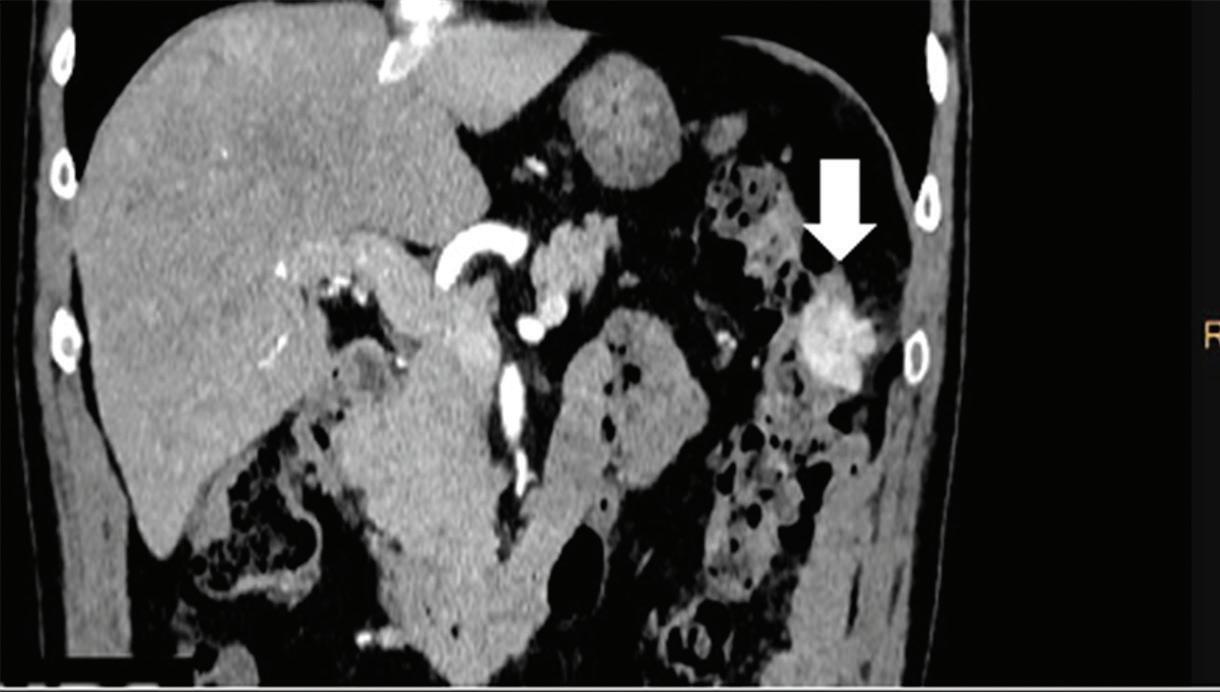

Z effective

Spectral CT is able to generate Z effective images that show the mean atomic number of the material present in a voxel (Z effective values) and can be displayed as color coded overlay maps. Z effective images may be helpful to enhance the visual differences between different tissue types.46 Furthermore, due to the high atomic number of iodine compared to other tissues present in the human body, the Z effective images can highlight enhancing structures (Figures 2, 3, 4, and 5) and could be used for quantitative analysis to differentiate benign from malignant tumors or lymph nodes.16,45,47

Multifocal HCC treated with sorafenib. (a) A small nodule (arrow) is barely seen on conventional axial CT image, acquired at late arterial phase after administration of 70 ml of contrast material (iodine concentration 350 mg/ml). (b) Monoenergetic 50 keV and (c) Z effective images improve the detection of this small nodule as well as allowing better evaluation of the peripheral solid component of both nodules seen in these images, with a precision comparable to that of (d) post contrast MR image.

Liver tumors. Use of low-monoenergetic images on late arterial phase improves the detection of hypervascular liver lesions (e.g., HCC in cirrhotic liver) (Figure 4).3,17,52,53 It also improves detection of hypovascular liver metastases on portal-venous-phase.54